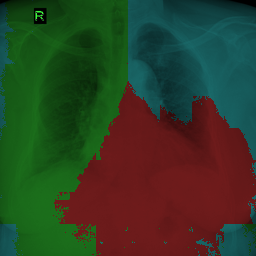

5.2.3 Results

Compared with the experiments in Sec. 5.1, we use a more extreme setting to test the limit of partially supervised methods. We use only 10 images from P (i.e. 10 images with optic cup annotated) and images from F (i.e. images with both optic disc and optic cup annotated). There is a severe class imbalance here, as the ratio of the number of labels for cup to the number of labels for disc is . The results measured in mIOU between the prediction masks and ground truth masks on optic disc and optic cup are presented in Table 6. With much smaller data size than before, EL fails. Besides, as EL is not designed for fully labeled datasets, the images with complete labels (from F) actually have a negative influence on the training. Meanwhile, PaNN cannot easily learn the image prior based on only a few fully labeled images. VLUU outperforms EL and PaNN by a large margin. Essentially, EL and PaNN do not solve the data scarcity problem, while VLUU can generate new vicinal examples. Moreover, a segmentation network trained with VLUU can even achieve comparable performance with the same network trained with complete labels (i.e. more supervision). Considering the existence of class imbalance and dataset shift, we conclude that VLUU is more robust on small-scale data. The visual comparison between PaNN, VLUU and Oracle is shown in Fig. 9. It can be seen that PaNN generates unrealistic shapes for the optic disc and optic cup if not enough fully labeled data is available learn a reasonable image prior. Note, although VLUU can achieve comparable performance with Oracle in numerical results, there are artifacts caused by the uncertainty of the vicinal labels, e.g. as shown in Fig. 9, VLUU may generate optic cup predictions outside the optic disc.